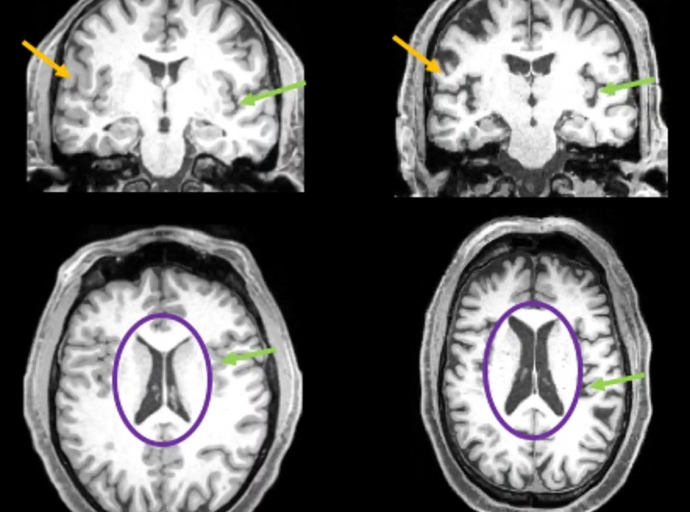

Incluso los casos ligeros de covid dejan marcan permanentes en el cerebro.